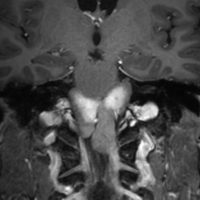

5歳の時に発見され23歳まで18年間経過観察をされてきた患者さんです。腫瘍はゆっくり,しかし確実に増大して,手術前には頭痛がひどく薬も効かず歩けなくなったという症状でした。術後に頭痛が無くなったので,のう胞による症状だったのでしょう。

下垂体柄の周囲にのう胞性腫瘍があります。T1強調画像では等信号,T2強調画像ではまだらな信号になっています。23年という長い経過から液状内容物が固形化したものと推定されます。T2で低信号となる部分があるのですが,黄色肉芽腫とは異なる像です。

下垂体柄は長く伸びています。のう胞による長期の圧迫のため斜台上部がerosionになって凹んでいます。トルコ鞍内の中間葉の位置に典型的な小さなラトケのう胞(黄色矢印)がみられますが,これは長年変化していませんでした。